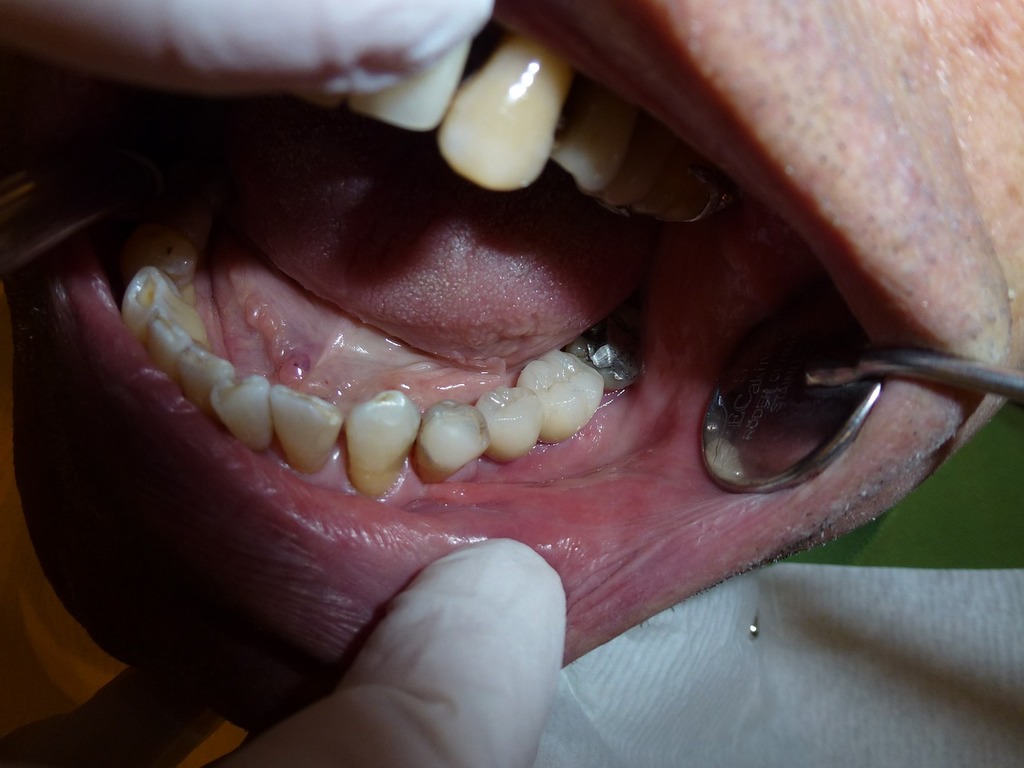

Það ætti að leggja þessar tanngreiningar algerlega niður og ganga einfaldlega út frá því að flóttafólk gefi réttar upplýsingar um aldur sinn. Ef þú ert 17 ára eða yngri þá ertu meðhöndlaður sem barn. Þú færð vernd og þarft ekki að ganga í gegnum þriðju gráðu yfirheyrslu til þess. Þú færð menntun, heilsugæslu, mat, húsaskjól, aðstöðu til tómstundastarfs og allt annað sem börn þurfa.